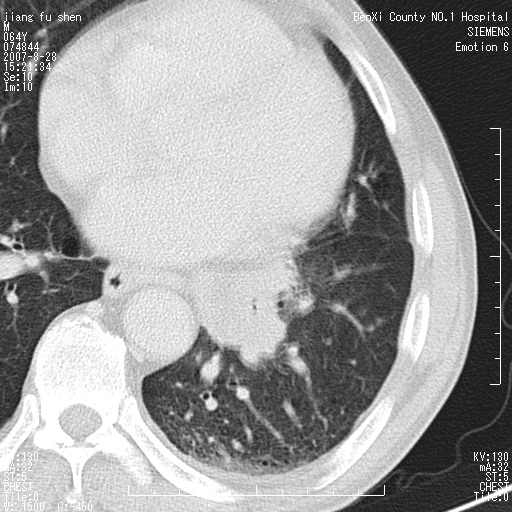

男、64、咳嗽、发烧一周、左肺呼吸音稍弱。既往肺结核,右手结核。

本次扫描患者未带原片,左肺下叶发现病灶。左肺上叶空洞,5组淋巴结肿大,1cm左右。

追问病史三月份ct扫描左肺上叶空洞,医大诊断肺结核。

平扫20-33hu

增强31-33hu

1分半44-52

2分55-67

左肺下叶前内基底段支气管明显偏心性狭窄,周围分叶状肿块,伴有阻塞性肺炎,支持肺癌可能性大。

考虑左肺中央型肺癌并阻塞性肺炎

考虑左肺中央型肺癌并阻塞性肺炎,建议纤支镜检查

病灶边缘可见多量较长棘影及纤维条索状影,除外病灶边缘较光整,病灶有分叶表现,但多表现为较浅分叶,且向周围伸出之叶多呈尖角改变,且边缘较光整,病灶增强呈中度延时增强,且早期及中期仅轻度增强,结合患者病史,多考虑继发型肺结核,炎性增殖灶形成,不除外肺癌

左肺下叶中央型肺癌